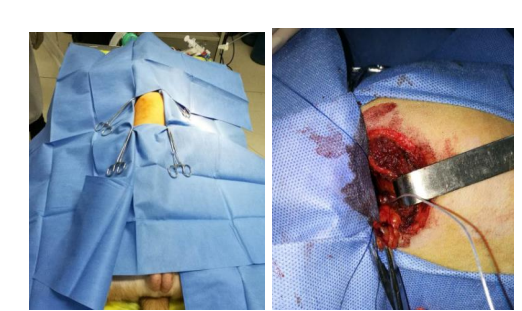

团队构建犬的慢性房颤动物模型,分析无创体表心电标测和有创心外膜心电标测系统采集的心电信号的相关性。我们通过经颈静脉介入(图10)和右外侧开胸小切口(图11)两种方法建立快速起搏右心房的犬慢性房颤模型

图10 经右侧胸部小切口构建右心房快速起搏犬的慢性房颤模型